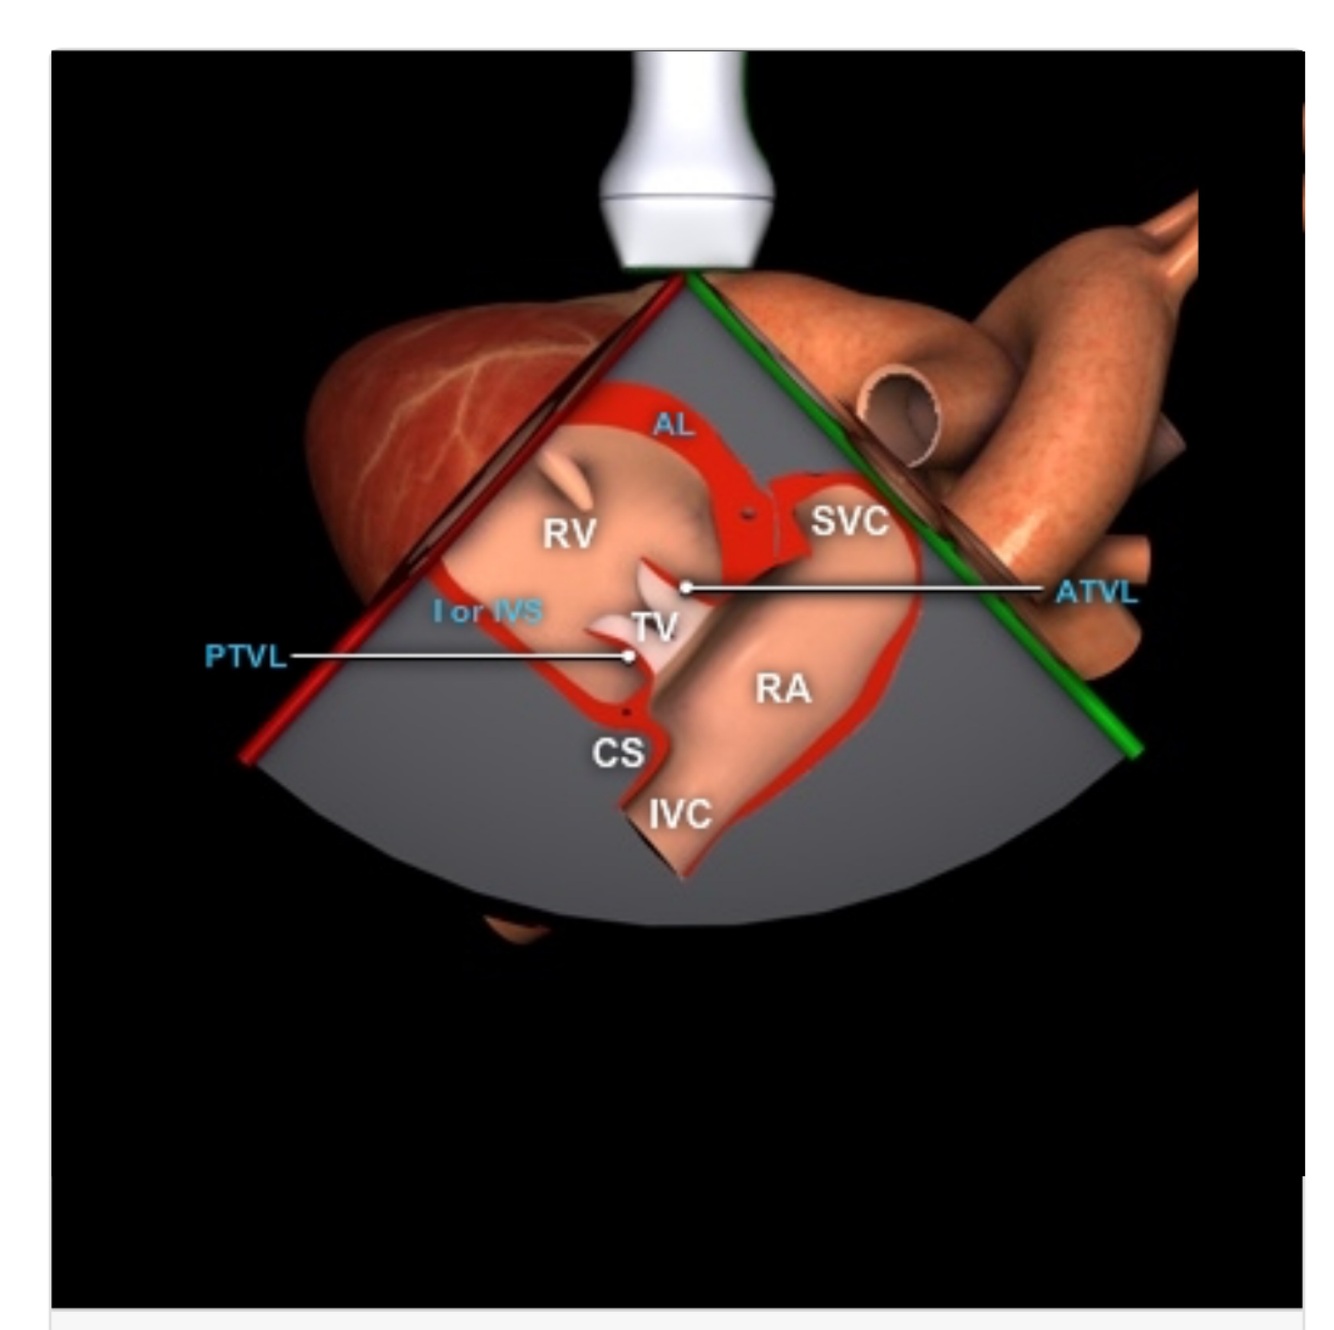

PLAX RV inflow

A